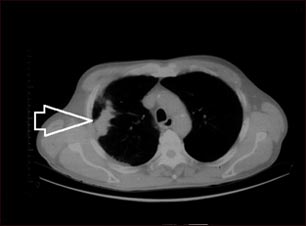

Masa pulmonar, pulmón derecho - Tomografía.

TC de la parte superior del tórax que muestra una masa en el pulmón derecho (se puede observar al lado izquierdo de la imagen).